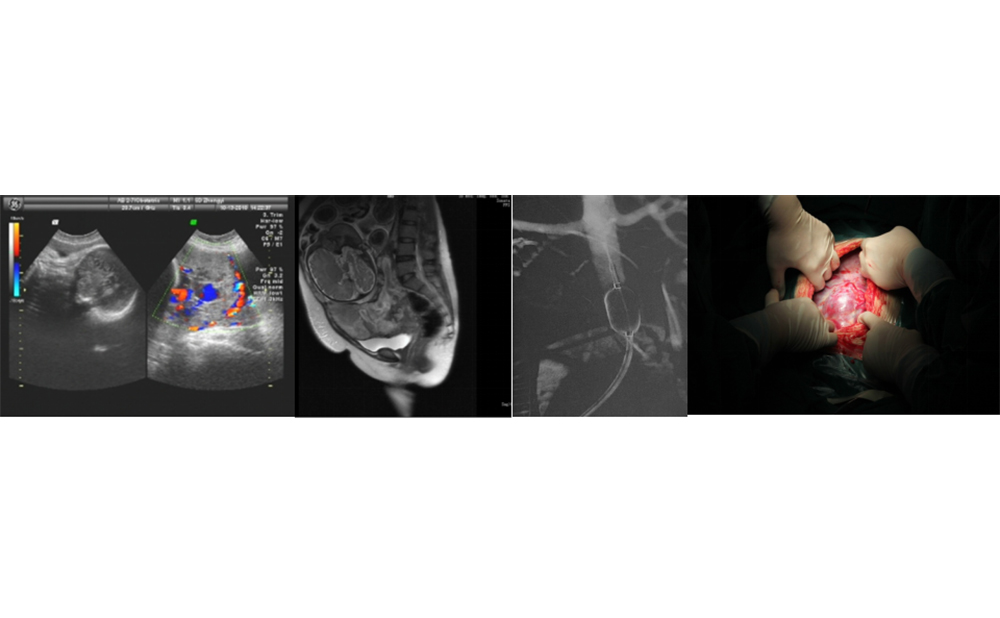

胎盘植入